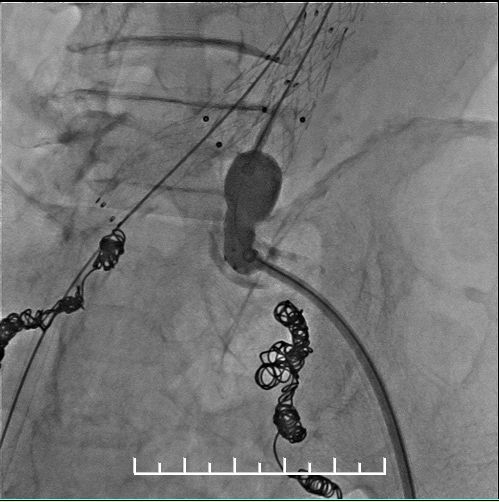

Ib型内漏(远端漏),需要处理

左右分别使用13.5*80、13.5*60mmFluency延长。左侧支架一定要越过髂动脉弯曲处,否则容易闭塞。此处可以看到左侧支架远端稍微有弯曲折叠。

仍然漏

不慌,还可以使用顺应性球囊扩张。

髂动脉硬化严重

再次造影:右侧髂支未显影!!!

是否近端原因,扩张一下

造影显示同样的结局

鞘管逆行造影,支架远端没问题,右侧股动脉搏动也正常。考虑血管扭曲,鞘管影响所致。

所以我们拔出右侧导管,缝合穿刺点。再次造影:显影良好,流速正常。